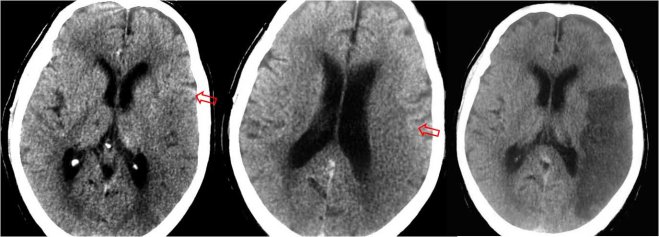

SIGNO DE LA PÉRDIDA DE DIFERENCIACIÓN SUSTANCIA GRIS-SUSTANCIA BLANCA

Las dos primeras imágenes muestran una pérdida de la diferenciación entre sustancia blanca y sustancia gris en el territorio de la ACM izquierda. Las flechas marcan la zona de interrupción de la diferenciación. La imagen de la derecha corresponde al estudio a las 24 horas, con el infarto claramente establecido.

Signo de infarto isquémico cerebral que puede estar presente en la fase precoz (menos de 6 horas desde el inicio) del accidente cerebrovascular, siendo en ocasiones el único signo presente. Es debido a la presencia de edema en el territorio infartado y consiste en la homogenización de las densidades de las sustancias blanca y gris.